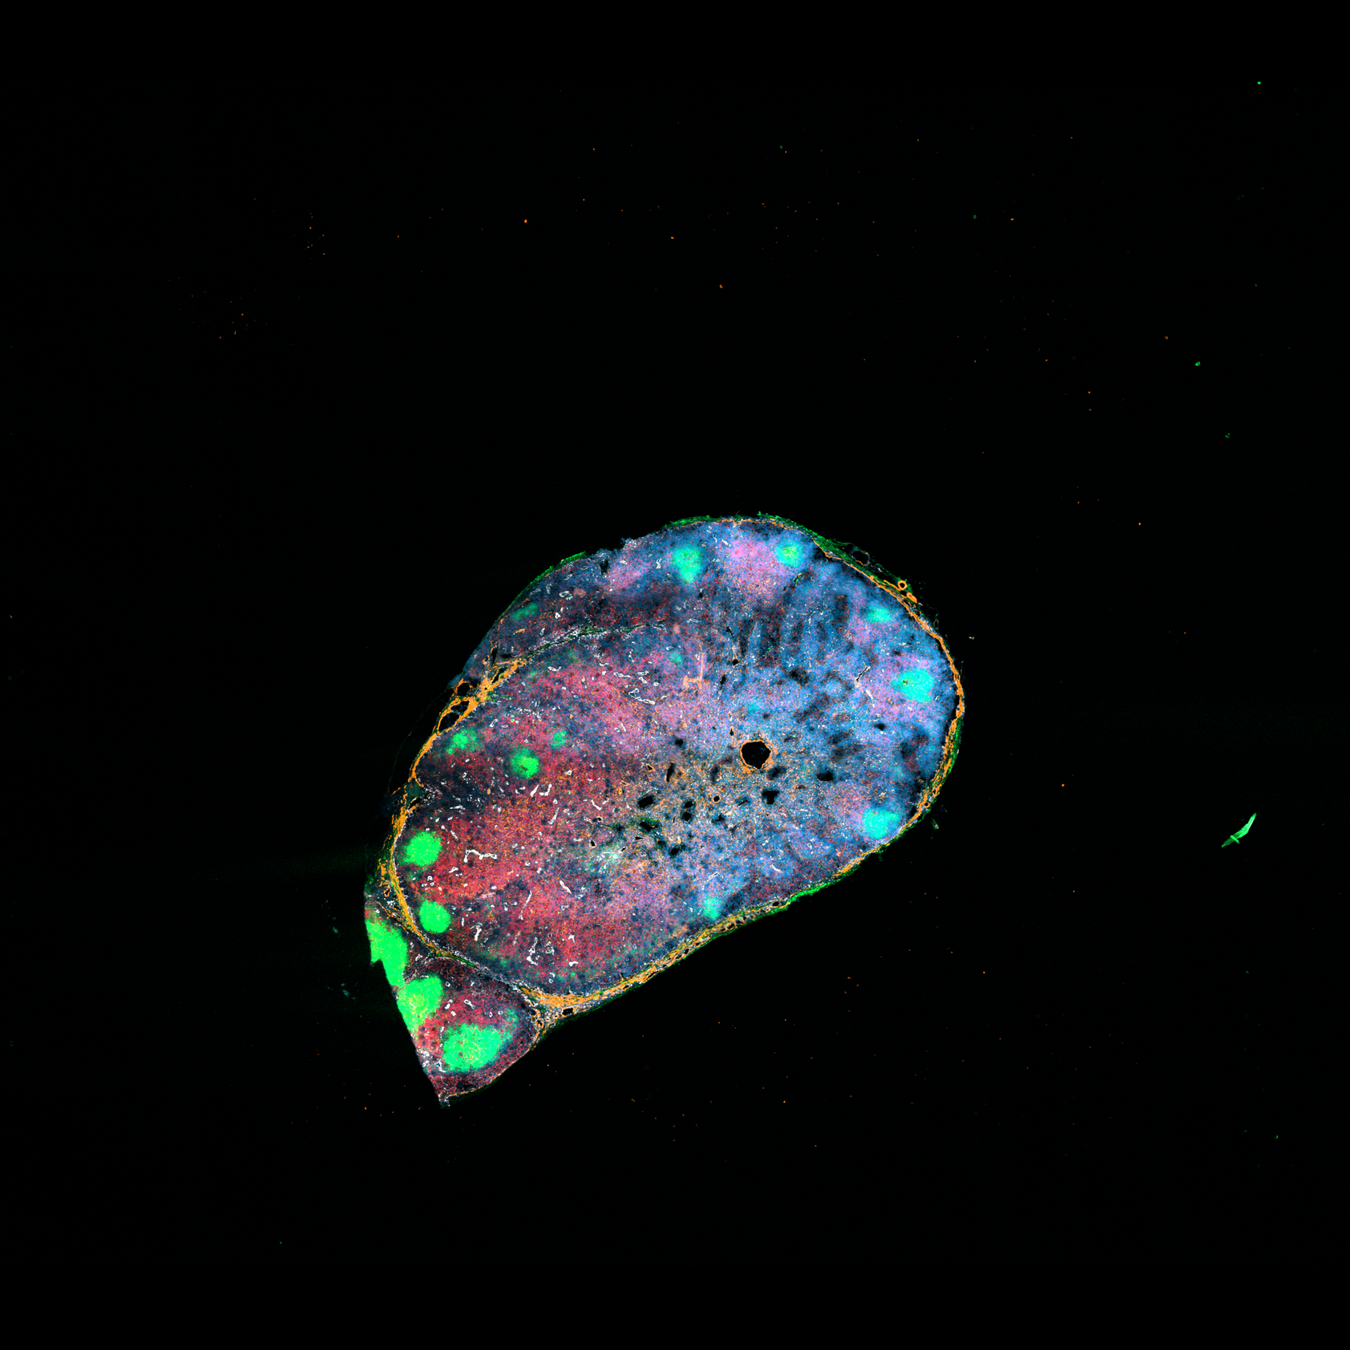

Localization of perivascular reticular cells in human lymph nodes using spatial transcriptomics and scRNAseq data → tool for celltype decomposition

Perivascular reticular cells

Histological images, biological knowledge about lymph node architecture

Spatial transcriptomics + single cell reference

SpaTalk, RCTD (spacexr)

SpaTalk:

Decomposition based on non-negative linear model

RCTD:

Maximum-likelihood estimation to resolve a statistical model that estimates mixtures of cell types at each pixel assuming gene counts to be Poisson distributed

Define evaluation criteria:

- B cell, T cell, endothelial cell position

- Expression of marker genes

- Known fibroblasts compartments

- Celltype proportions from FACS data

- Both tools achieve robust and comparable outputs

- SpaTalk closer in resembelling celltype proportions

PRC

RCTD

SpaTalk

T cell

B cell